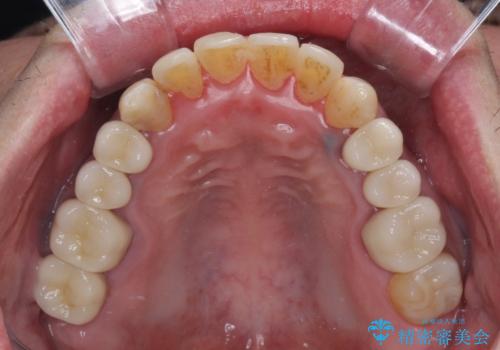

- 飛び出している上顎前歯と、奥歯に多くある銀歯を気にして来院された患者様です。

マウスピースで矯正を行いたい反面、一旦早めに前歯を整えたいというご希望があったため、まずは上顎前歯をワイヤー装置で整え、その後インビザラインにて仕上げていくこととしました。

矯正治療後には、奥歯の銀歯をすべてセラミックにて補綴治療することとしました。

ワイヤー矯正を併用したことで、上顎前歯はあっという間に整いました。

補綴治療にあたり、痛みのある歯に対して根管治療を行うこととしましたが、処置が必要な歯が多かったため、期間を要しました。

補綴治療中に前歯のデコボコが戻ってしまったため、補綴治療後にインビザラインを1セット追加して仕上げました。